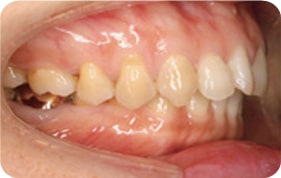

Case 4

2017. 08. 04

2017. 12. 15

2018. 02. 10